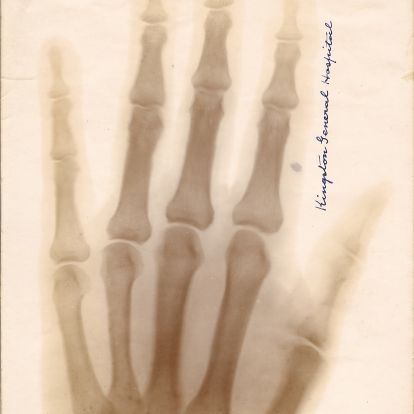

The arrival of X-ray technology

X-rays first made their appearance in Kingston on February 17, 1896, when the Weekly Whig reported that Captain John Bray Cochrane (1860-1946), Professor of Physics and Chemistry at the Royal Military College, had taken an x-ray image of the hand of Madame Emma Albani, a celebrated singer, as a demonstration.

Cochrane first applied the diagnostic power of the x-ray to a medical case in May of 1896. A patient named Miss Hooper had run a sewing needle into her palm, which subsequently became so swollen that physicians could not identify the location of the needle to extract it. Cochrane took two x-rays of the hand at RMC, each requiring 12 minutes of exposure, clearly identifying its location. Then, KGH surgeon Dr. R.K. Kilborn, was able to remove the needle.

Later that year, under Medical Superintendent Dr. James Third (1865-1925), KGH recruited Cochrane as the hospital’s first cathographer and acquired its own x-ray equipment. KGH became the second Canadian hospital to purchase x-ray apparatus for medical use and records suggest that patients travelled to Kingston from as far as Buffalo, New York to benefit from the technology.

An early X-ray print of a hand